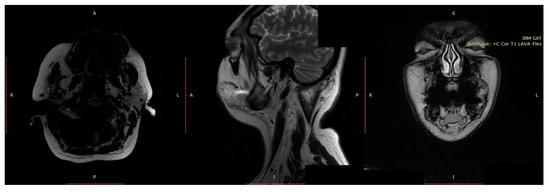

3.1.2. Diagnosis

3.3.2. Diagnosis